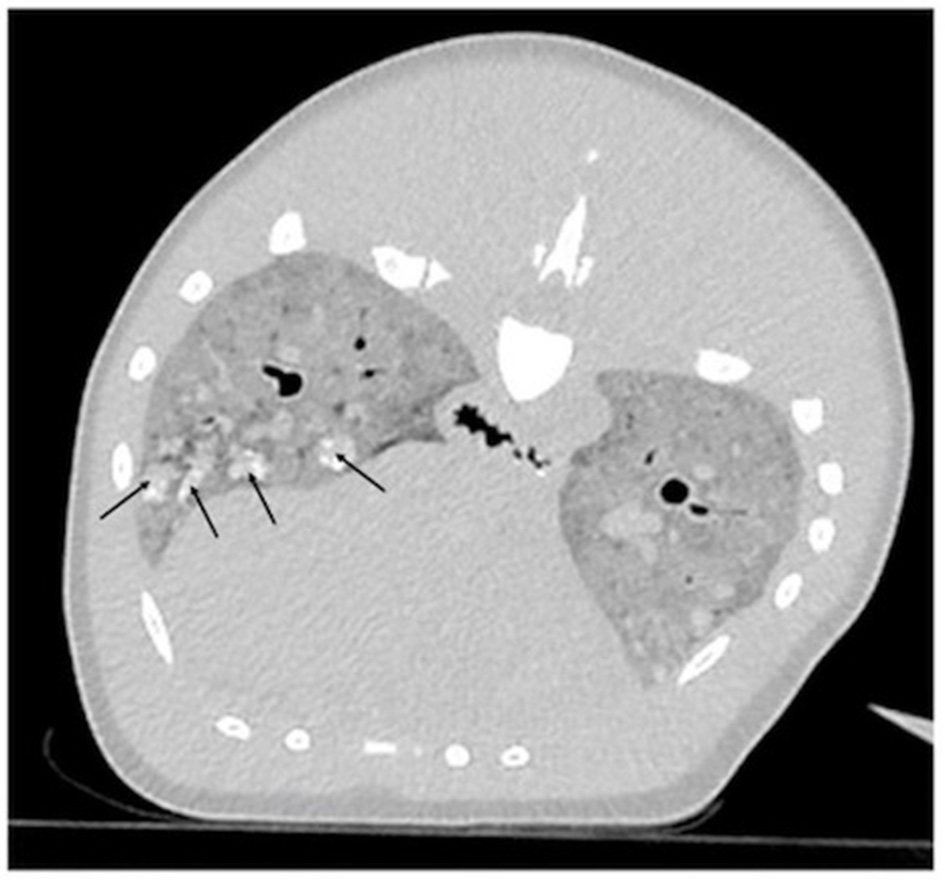

Endotracheal intubation for lung expansion was not performed prior to imaging due to the technical difficulty of intubation in a dolphin of this size. CT images revealed that the pulmonary parenchyma had severely increased soft tissue attenuation bilaterally (Figure 1). The diffuse changes in the pulmonary parenchyma were attributed to postmortem atelectasis. Within the lungs there were numerous small, poorly-defined, rounded soft-tissue attenuating nodules, some with mineral attenuating foci (Figure 1). The nodules measured up to 2 centimeters in diameter. These represented antemortem lesions, and the differential diagnosis included chronic granulomatous pneumonia of fungal, parasitic and/or bacterial etiologies. Visible abnormalities were absent from the central nervous system.

Computed tomographic (CT) transverse image centered on the mid-thorax reconstructed in a lung algorithm of an adult male Stenella frontalis. Diffusely, the pulmonary parenchyma has a severe increase in soft tissue attenuation and contains multifocal and ill-defined soft tissue attenuating nodules, some of which have mineral foci (black arrows).